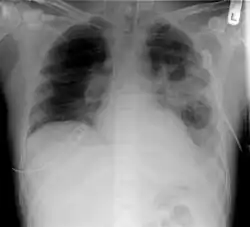

- A maioria das infecções por vírus, bactérias, como por exemplo Constipação/Resfriado, gripe, infecções gastrointestinais, pneumonia, meningite.